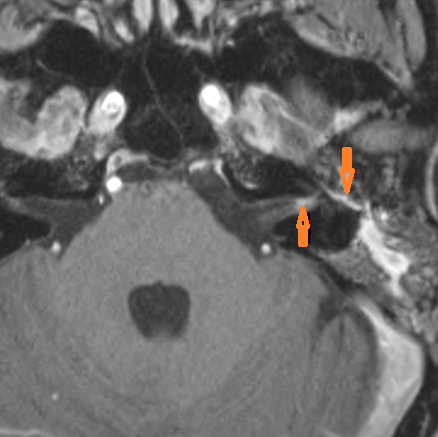

There are localized fluid collections in the deep soft tissues involving the nasopharynx and/or the parapharyngeal, masticator, retropharyngeal and prevertebral spaces. [Yes/No]

General Skull Base

There are localized, potentially subperiosteal, fluid or pus collection spreading along the petrous apex inferior surface (mainly below the carotid canal) and/or clivus. [Yes/No]